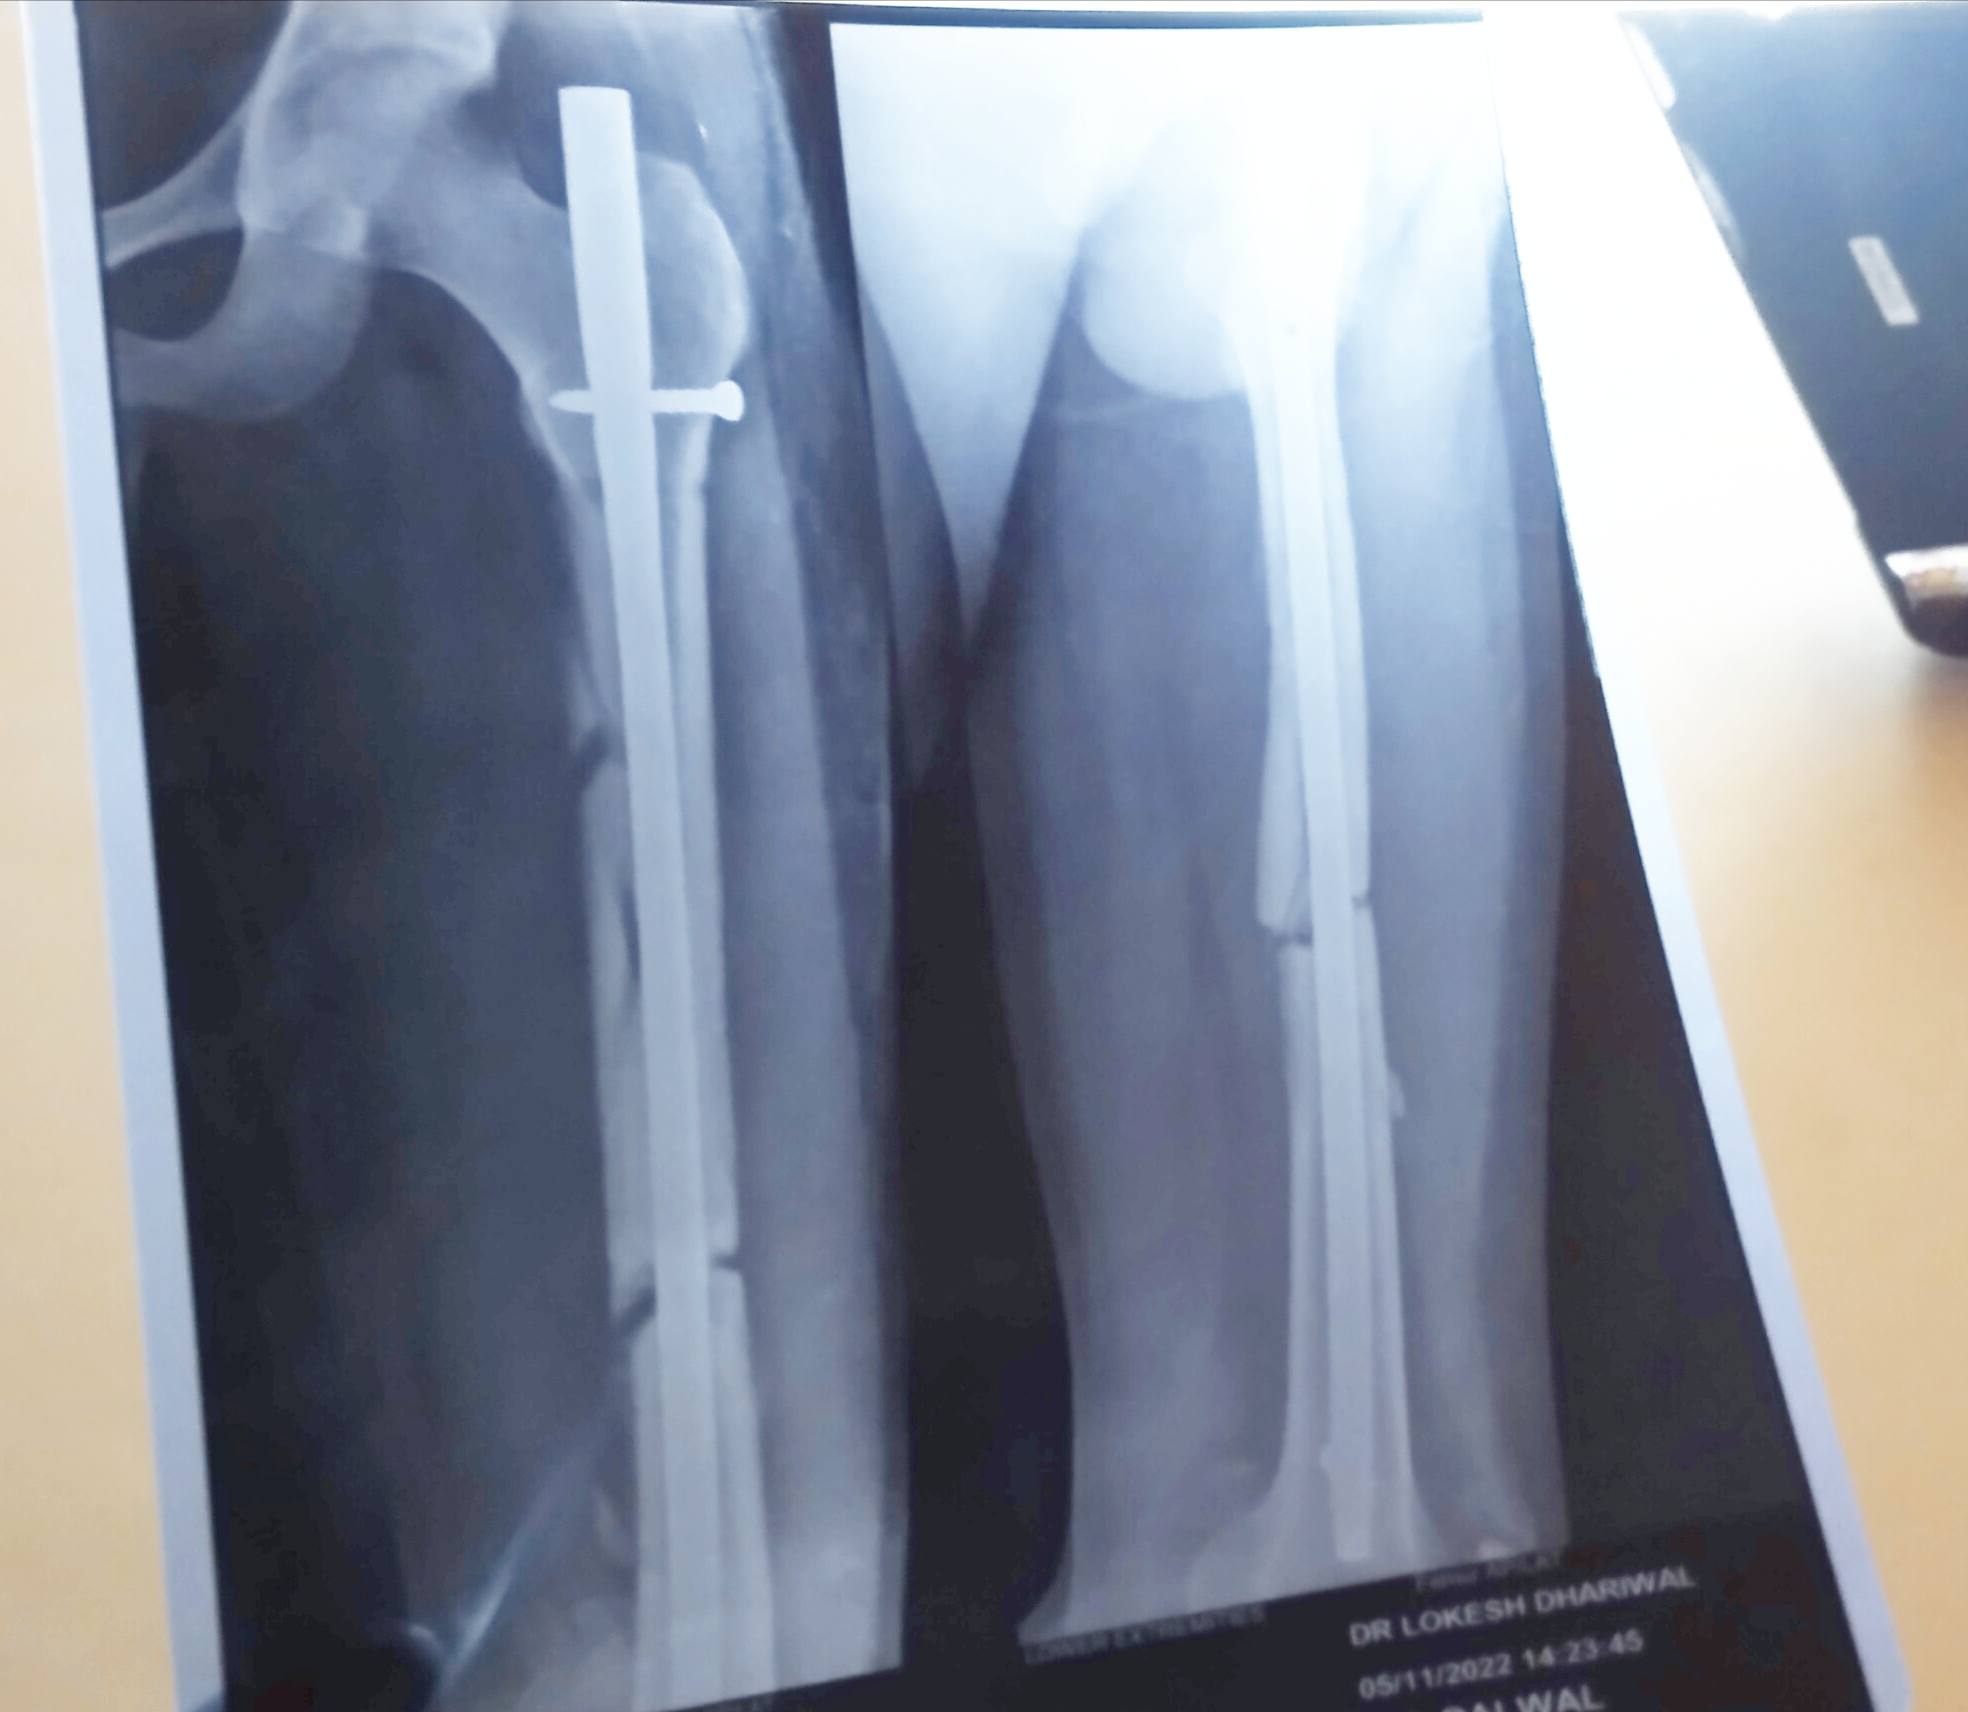

Sir i want to say that my 1st month x ray after surgery is same with the fresh x ray of 2.25 month after surgery.what should i have to do